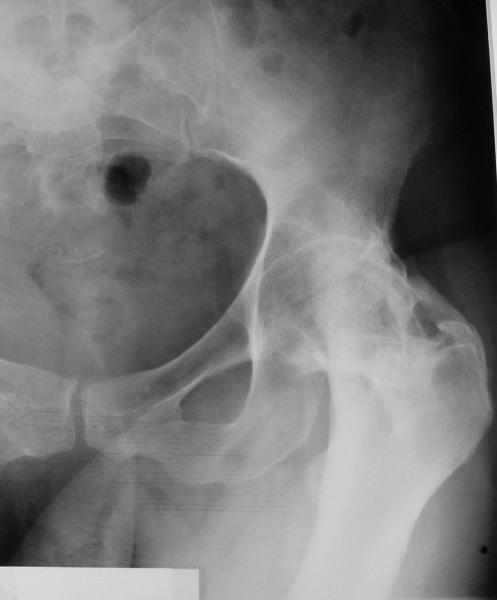

У больной 53 лет в последний год появились сильные боли в пояснице.

При обследовании выявлен анкилоз тазобедренного сустава в приведении. Видимо, в период пребывания в тяжелом состоянии появились гетеротопические оссификаты. За исключением того, что осталась одна почка, сейчас других медицинских проблем нет.

Пациентку в первую очередь беспокоят боли в спине, на отсутствие движений в суставе она вроде и не жалуется. Вопрос насчет тактики. Корсет и анальгетики вряд ли решение. Первый вариант - удаление оссификатов и эндпротезирование, второй - корригирующая остеотомия в проксимальном отделе с устранением порочного положения.

Второй вариант много проще и менее травматичен. Можно ли без размыкания сустава рассчитывать на существенное уменьшение боли за счет устранения перекоса таза?

Я думаю, что эндопротезирование - более предпочтительный вариант у пациентки 53 лет. К тому же суставная щель прослеживается и, вероятнее, большой сложности с установкой вертлужного компонента не будет. Высока вероятность необходимости аддуктотомии.